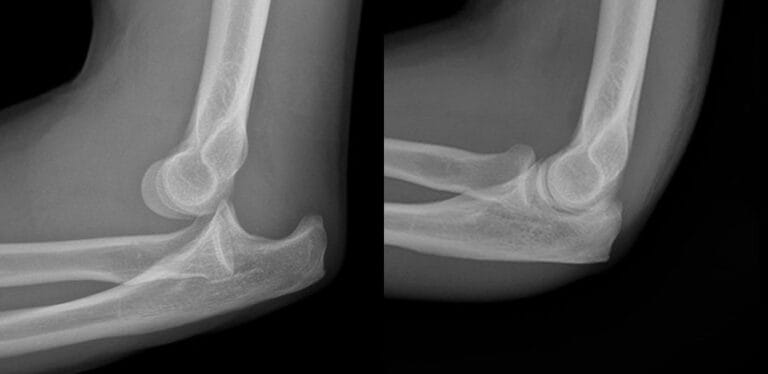

- Symptoms: There will be a noticeable deformity, pain, and difficulty moving the arm. The elbow may look bent out of shape.

- Diagnosis:

- X-rays: Used to check for any broken bones and ensure the joint is properly aligned after fixing the dislocation.